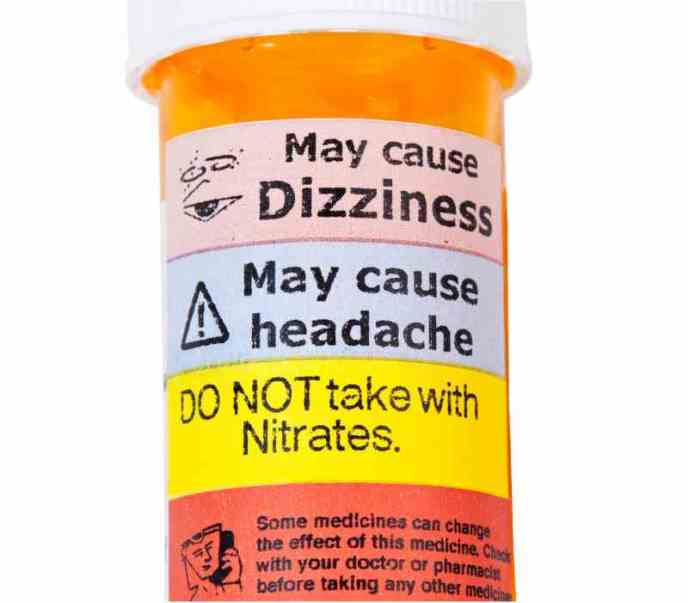

images.lifescript.com

Side Effects of Tramadol: Some of the common symptoms you may experience after taking tramadol include bloating, nausea, increased blood pressure, chills, and stomach or abdominal pain. You may also experience fainting, blood in urine, loss of memory, and increased heart rate.

In cases of chronic pain, doctors recommend adults to take 100mg once a day. For severe or moderate pain, doctors may recommend 50 to 100 mg every six hours. It is also important to read the label and avoid increasing the dosing without consulting your doctor.

Precautions: If you are already taking tramadol, it is best to stop taking other painkiller medications to avoid an adverse reaction. Tell your doctor all types of medication you are currently taking when you are prescribed tramadol.